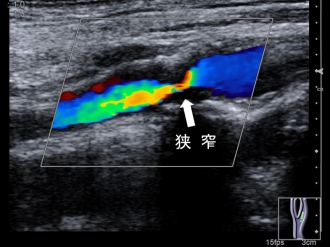

シャントの血流量や狭窄の有無などを観察します。

透析シャント

検査内容